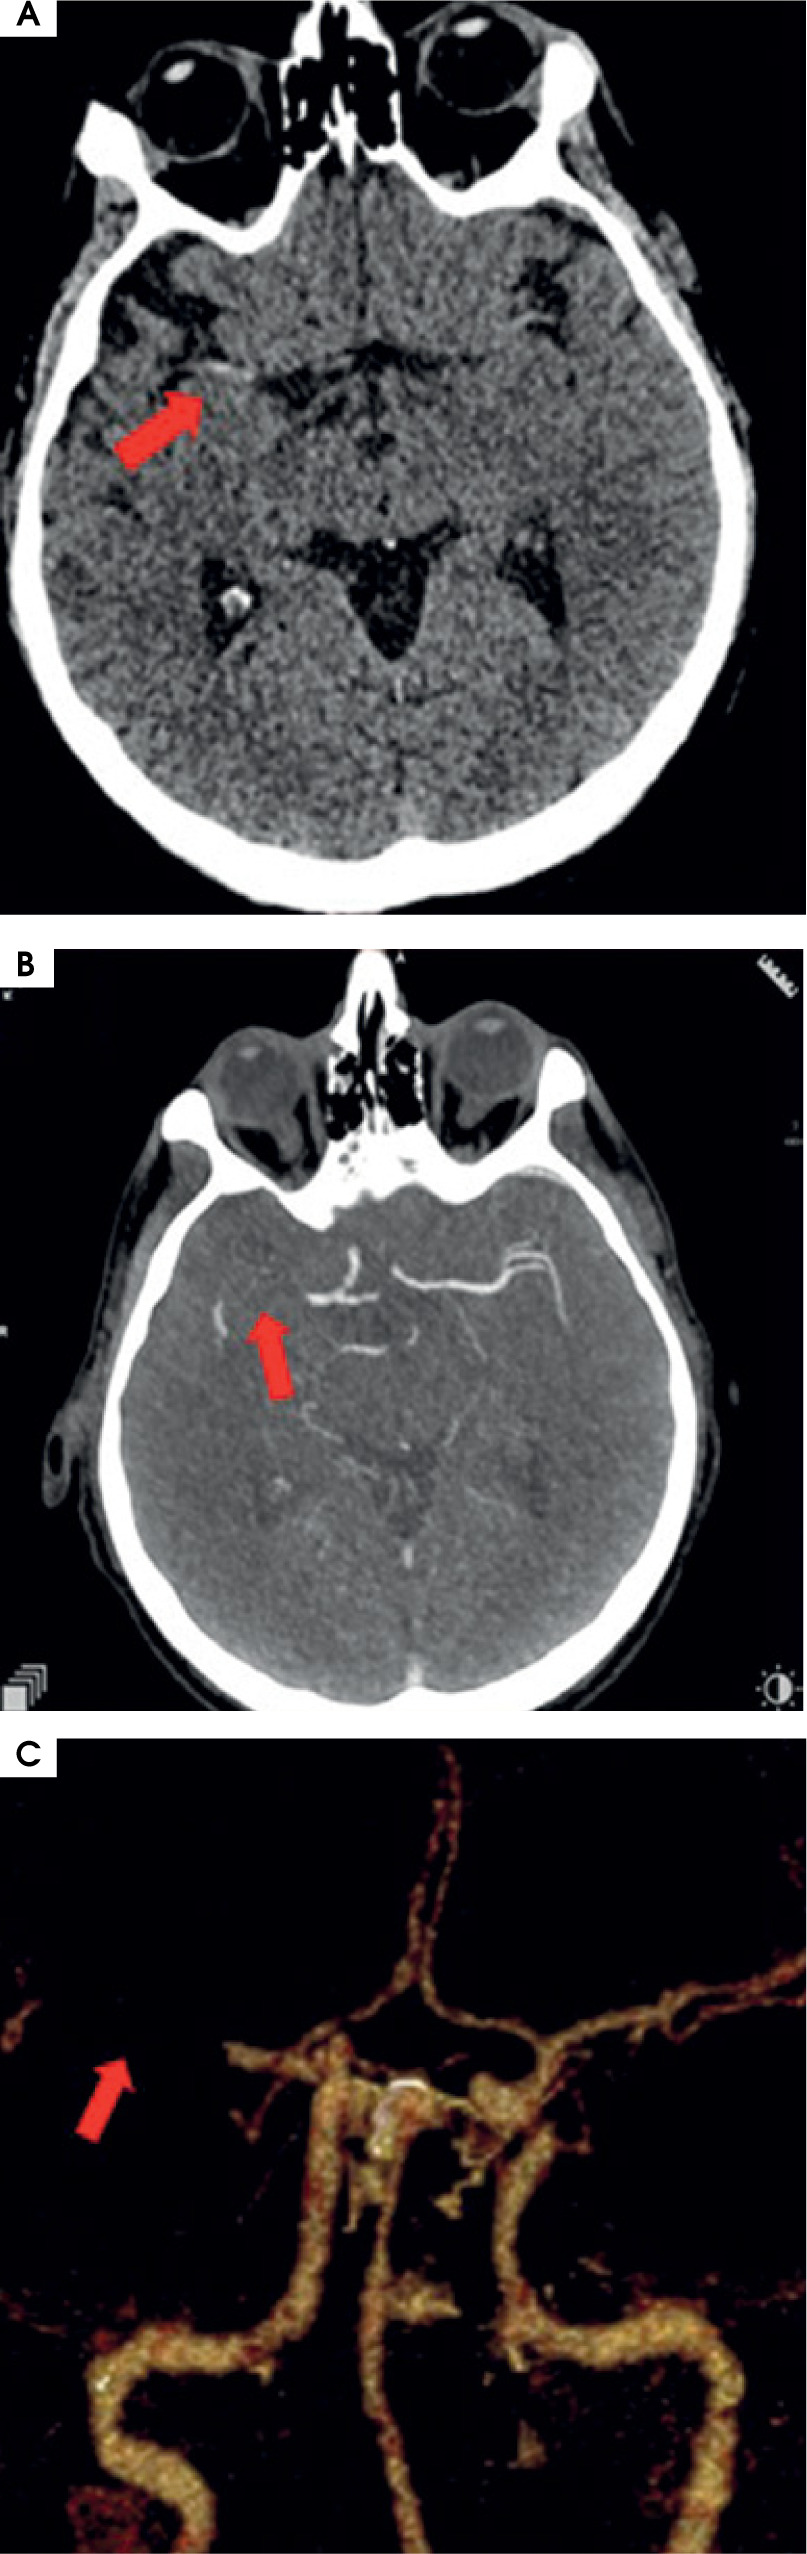

Twelve hours after admission to ICCU, in the presence of medical staff, the patient experienced symptoms of the stroke such as dysarthria, drooping of the corner of the mouth at the left side, and severe weakness of the left upper and lower limbs. The computed tomography (CT), which was performed immediately, showed that a high attenuation of the right middle cerebral artery (RMCA) was present (Figure IA). Angio-CT of cerebral arteries confirmed the occlusion of RMCA at segment M1/M2 about 6.5 mm from the origin of RMCA (Figure IB). The VRT (volume rendering technique) reconstruction of cerebral arteries was performed based on angio-CT (Figure IC).

Figure I

A) Computed tomography without contrast – hyperdense right middle cerebral artery (RMCA). B) Angio-CT – occlusion of RMCA in M1/2 segment. C) VRT (volume rendering technique). Arrows show pathological lesions